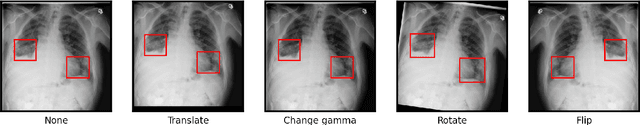

Abstract:Deep learning semantic segmentation algorithms can localise abnormalities or opacities from chest radiographs. However, the task of collecting and annotating training data is expensive and requires expertise which remains a bottleneck for algorithm performance. We investigate the effect of image augmentations on reducing the requirement of labelled data in the semantic segmentation of chest X-rays for pneumonia detection. We train fully convolutional network models on subsets of different sizes from the total training data. We apply a different image augmentation while training each model and compare it to the baseline trained on the entire dataset without augmentations. We find that rotate and mixup are the best augmentations amongst rotate, mixup, translate, gamma and horizontal flip, wherein they reduce the labelled data requirement by 70% while performing comparably to the baseline in terms of AUC and mean IoU in our experiments.